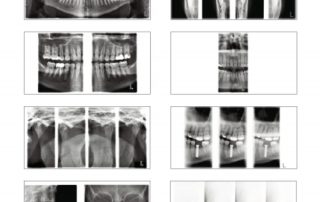

The three-joint Planmeca ProMax 2D S3 unit has been designed for all 2D imaging needs: panoramic, true extraoral bitewing, TMJ, sinus and 2D tomographic imaging.

While the two-joint ProMax 2D S2 panoramic imaging unit includes basic programs for panoramic, extraoral bitewing, TMJ and sinus imaging.

Extensive imaging programs

Planmeca ProMax 2D units offer the widest variety of imaging programs, including options for TMJ, sinus and tomographic imaging. The units also have a child mode that allows imaging at lower doses by reducing the imaging area and exposure values.